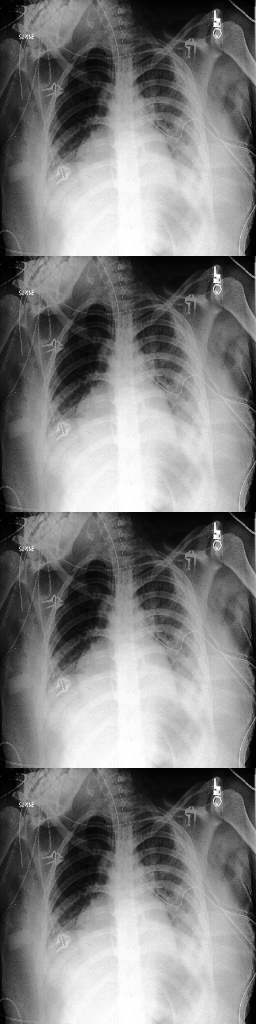

For the Chexpert dataset introduced in [12], we used a training set of 14179 images of healthy subjects and 16776 images of subjects that suffer from pleural effusions. The test and validation set each consist of 200 images for each class.

For classification, we compare DeScarGAN against the classification results of StarGAN, FP-GAN, Densenet169 [11] and the classifier Dclssubscript𝐷𝑐𝑙𝑠D_{cls} without the GAN mechanism. The result for the image-level classification is measured in classification accuracy, the Cohen’s kappa score [6] and the AUROC score. Further, we measure the MSE between real images rhsubscript𝑟r_{h}\in\mathcal{H} and artificial images ahsubscript𝑎a_{h}\in\mathcal{H}. The scores are summarized in Table 2.

Refer to captionInput rpsubscript𝑟𝑝r_{p}Refer to captionOutput ahsubscript𝑎a_{h}Refer to captionDifference |d|𝑑|d|Refer to captionInput rpsubscript𝑟𝑝r_{p}Refer to captionOutput ahsubscript𝑎a_{h}Refer to captionDifference |d|𝑑|d|Refer to caption11100DeScarGANFP-GANVAGANVAE

Figure 6: Comparison of our DeScarGAN against FP-GAN, VAGAN and VAE for two samples of the Chexpert dataset.

DeScarGAN achieves better classification results than the pure classification networks Dclssubscript𝐷𝑐𝑙𝑠D_{cls} and Densenet169, indicating that the GAN mechanism supports the classification network. The results of the different methods are visualized in Figure 6. We observe that the VAE fails to detect pleural effusions. Although FP-GAN detects similar regions as our method, the generated maps appear blurry and mark regions outside the thorax. The additive map of VAGAN also outlines parts of the arms and upper chest as abnormal. Our method generates the most detailed difference map, not highlighting any regions outside the pleural space.